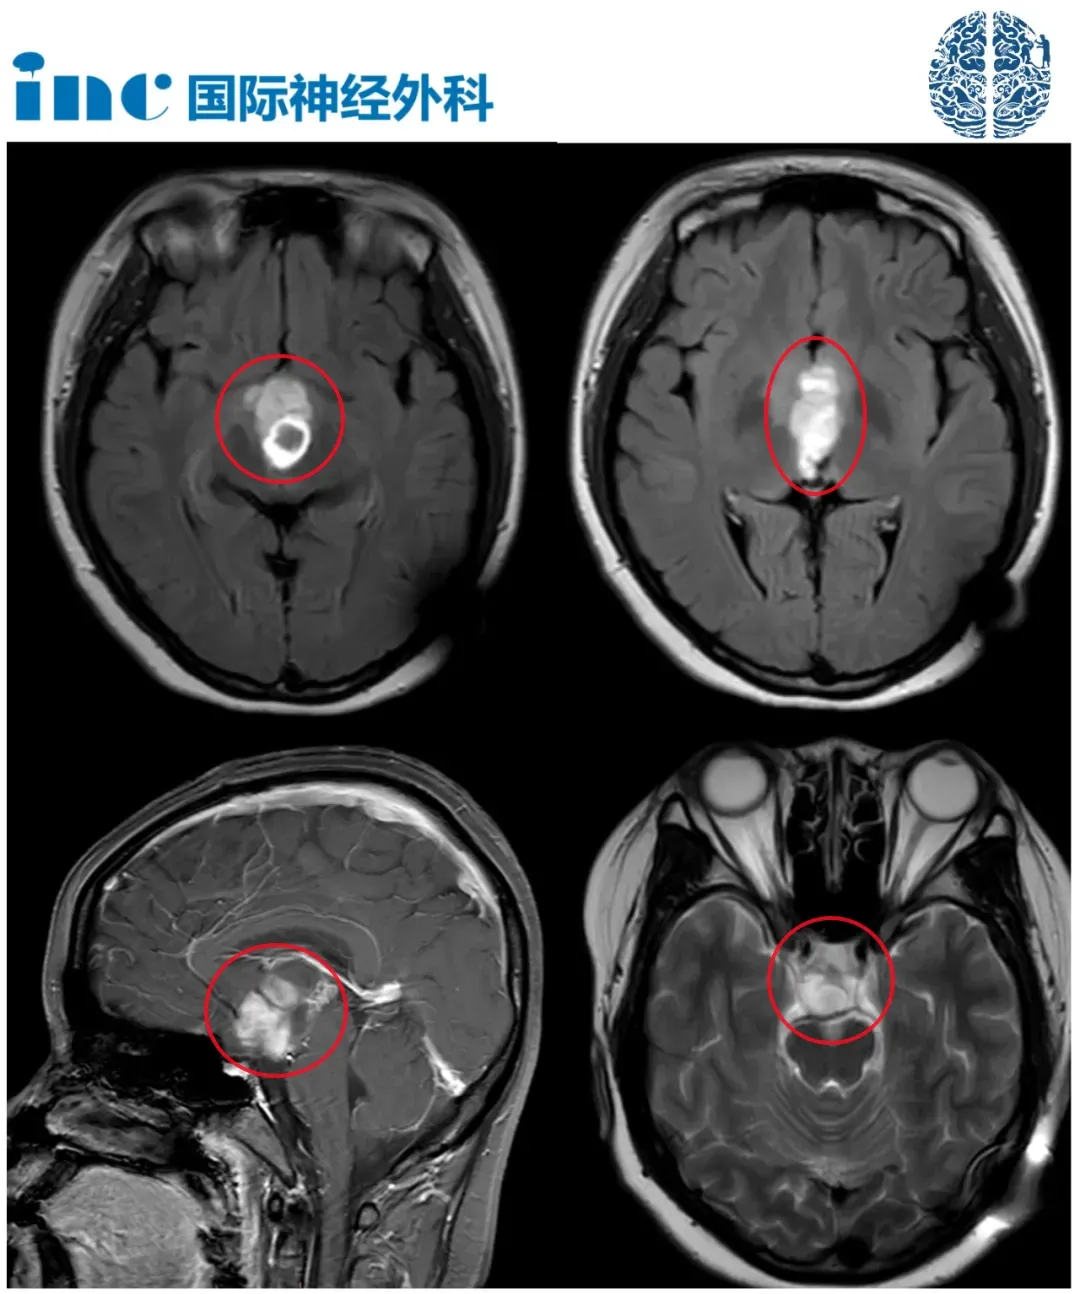

术后MRI

术后无新发神经功能损伤,视路、视交叉、下丘脑、嗅神经、穿支动脉都得到完整保留。